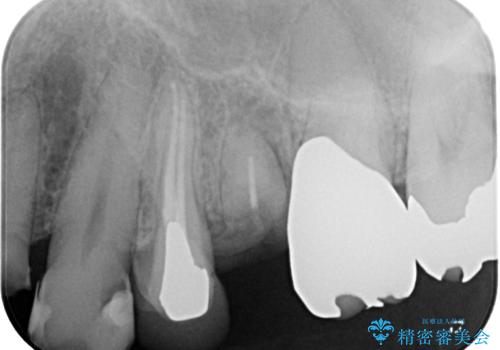

- 左上の小臼歯の被せものが外れてしまったことを主訴に来院された患者様の症例です。

診査・診断を行ったところ、

歯質の残存量(フェルール)が確保できない状態

歯根が短く、矯正治療で挺出を行っても将来的な予後が不良

と判断されました。

このようなケースでは、無理に被せ物をやり直しても再び脱離を繰り返したり、破折してしまう可能性が高く、長期的な安定は期待できません。そのため、今回は抜歯が最も妥当な治療選択と診断しました。